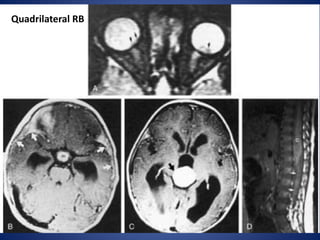

Quadrilateral (tetralateral) RB:

Bilateral disease plus pineal and suprasellar tumor

Quadrilateral RB

Trilateral RB: Bilateral oculartumors plus midline intracranial neuroblastic tumor, typically pineal Quadrilateral (tetralateral) RB: Bilateral disease plus pineal and suprasellar tumor

• #52 Tetralateral retinoblastoma. A, Axial T2-weighted MR image shows bilateral retinoblastoma (arrows). B, Enhanced axial T1-weighted MR image shows a markedly enhancing suprasellar mass (m). Note the subarachnoid spread of the tumor, seen as leptomeningeal enhancement along the sylvian fissures (arrows). C, Enhanced axial T1-weighted MR image shows marked enhancement of a pinealoblastoma (arrow). D, Enhanced sagittal T1-weighted MR image obtained a few months later shows diffuse distal spinal cord (C ) and subarachnoid metastases (arrows).